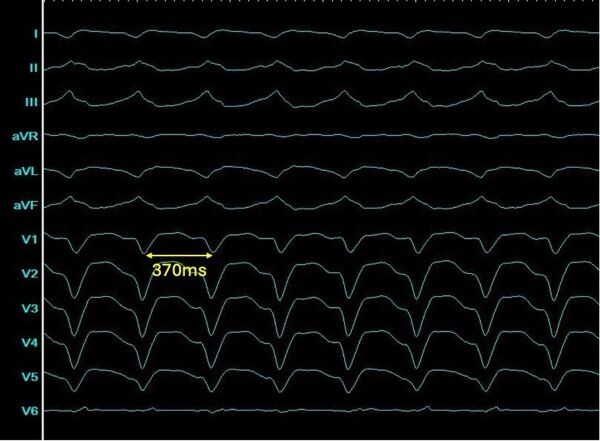

Die ICD-Abfrage zeigte mehrere VT-Episoden mit einer Zykluslänge (CL) von 370 ms. Eine Koronarangiographie ergab keinen Progress der bekannten KHK. Es bestand eine leitliniengerechte Herzinsuffizienztherapie mit Metoprolol, Sacubitril/Valsartan, Spironolacton und Dapagliflozin. Gemäß den aktuellen Leitlinien zur Behandlung der VT bei einem Patienten mit symptomatischen, anhaltenden, monomorphen ventrikulären Tachykardien trotz Betablockertherapie wurde Indikation zur erneuten VT- Ablation gestellt.

Die Untersuchung erfolgte unter Kardioanalgosedierung mit Propofol und Fentanyl. Das Voltage Map des LV im Sinusrhythmus zeigte ein ausgedehntes Areal mit Niedervoltage anterolateral und apikal sowie Nachweis von Spätpotentialen (Abb. 2A). Durch programmierte Stimulation konnte die klinische Tachykardie induziert werden (Morphologie: inferiore Achse, negative V1-V6, negative I; Abb. 1).

12-Kanal-EKG der ventrikulären Tachykardie (50 mm/s)

Abbildung 1: 12-Kanal-EKG der ventrikulären Tachykardie (50 mm/s)